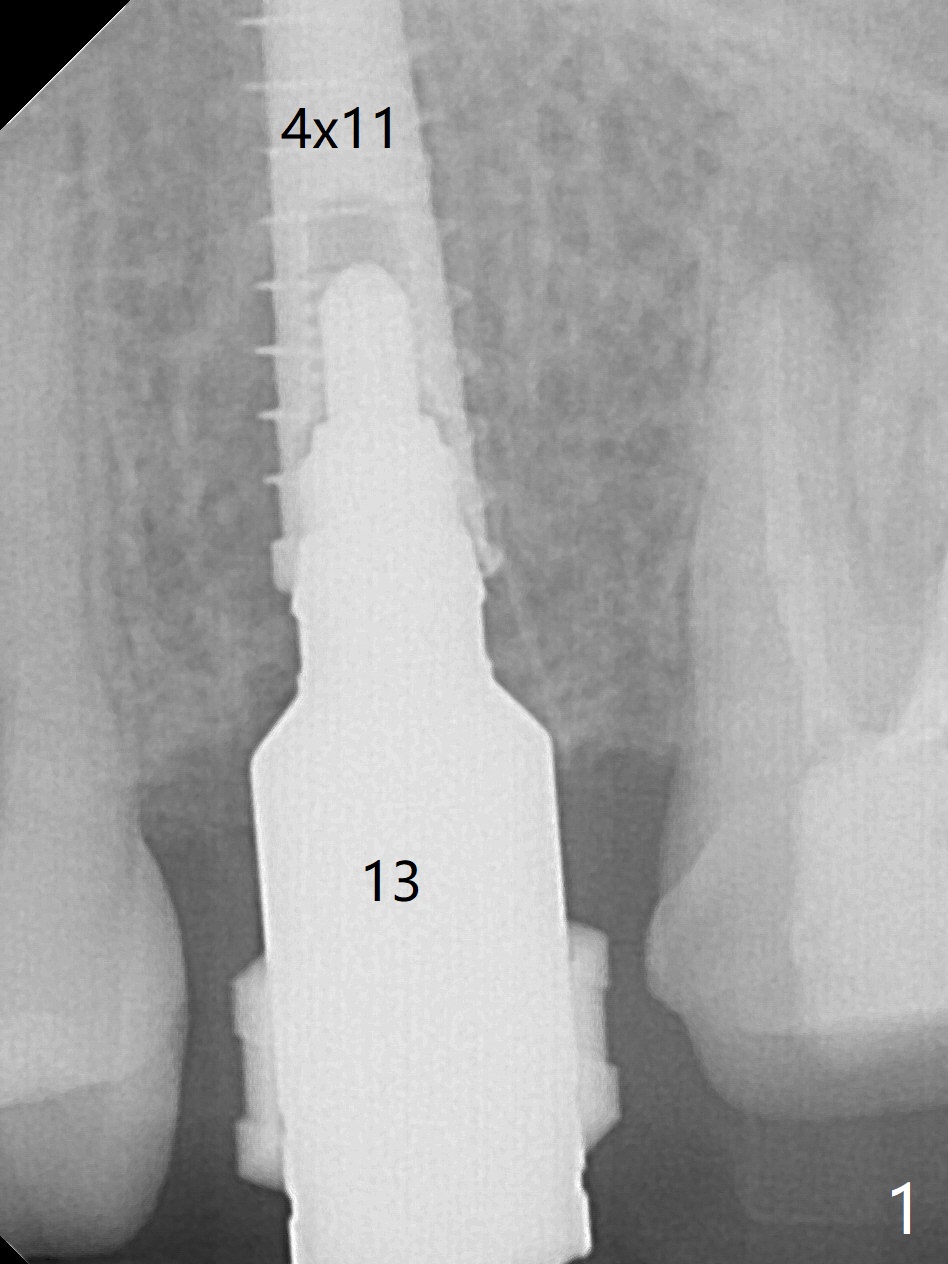

Due to misinterpretation of drill sequence, osteotomy is overprepared in depth (1.5 to 3 mm). When a 4x11 mm dummy implant is placed with > 50 Ncm (Fig.1,2), over placement is ignored. A 4x13 mm final implant is placed with fairly good torque, but it is deeper than expected. When it is backed up, primary stability is lost, in spite of placement of allograft in the osteotomy. Final torque is 15 Ncm. When a 4.5x4(2) mm abutment is placed, the underlying implant turns (Fig.3). A splinted provisional is fabricated at #13 and 14. RCT is retreated 5 months postop (Fig.4 *). An abutment with longer cuff is placed before impression (8.5 months postop, Fig.5). When the crowns of #13 and 14 are delivered, the former looks short and noncosmetic, although the gingiva will grow downward to close the gap (Fig.6). Ideally the gap should be closed with porcelain with overhang (Fig.7).